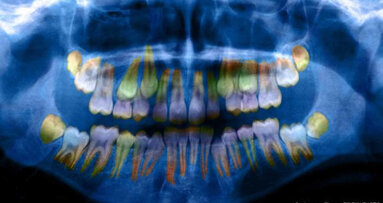

Likwidacja szkolnych gabinetów stomatologicznych odbiła się negatywnie na stanie zdrowia dziecięcych zębów. Coraz częściej jednak sami dentyści odwiedzają szkoły albo zapraszają dzieci do gabinetu, by nauczyć ich właściwego dbania o higienę, a przy okazji zbadać stan zębów. Jedna z takich akcji rozpoczyna się w Gliwicach.

Dzieci z gliwickich przedszkoli wezmą udział w specjalnie przygotowanych dla nich warsztatach stomatologicznych pod hasłem „Dentysta jest fajny”, podczas których nie tylko dowiedzą się, jak prawidłowo myć zęby, ale także będą miały okazję oswoić się z gabinetem stomatologicznym. „Nasza akcja to odpowiedź na potrzeby placówek oświatowych, które od dłuższego czasu nie dysponują gabinetami stomatologicznymi, a także próba stawienia czoła niepokojącym statystykom. Jak wynika z danych, 81% dorosłych Polaków boi się dentysty, zaledwie co 5. dorosły mieszkaniec naszego kraju wie, jak prawidłowo myć zęby, a ponad 90% społeczeństwa ma próchnicę. Te statystyki nie biorą się jednak znikąd. To efekt tego, jak dbamy o zdrowie jamy ustnej od najmłodszych lat. A dzieci boją się dentystów, nie potrafią dobrze myć zębów, do gabinetu przychodzą przeważnie z bólem, opuchlizną i płaczem. Większość dzieci ma próchnicę, gdyż rodzice wciąż myślą, że nie warto leczyć mleczaków skoro i tak wypadną” – wylicza lek. stom. Bartosz Nowak, pomysłodawca akcji.

Tymczasem, jeśli dziecku przedwcześnie wypadnie ząb, to może dojść do nieprawidłowego wyrzynania się zębów stałych i powstania wad zgryzu. Dlatego nie powinno się zostawiać niezabezpieczonej luki po utraconym zębie. Luka po utraconym mleczaku powinna być wypełniona za pomocą dziecięcej protezki lub też zabezpieczona przy pomocy utrzymywacza przestrzeni.